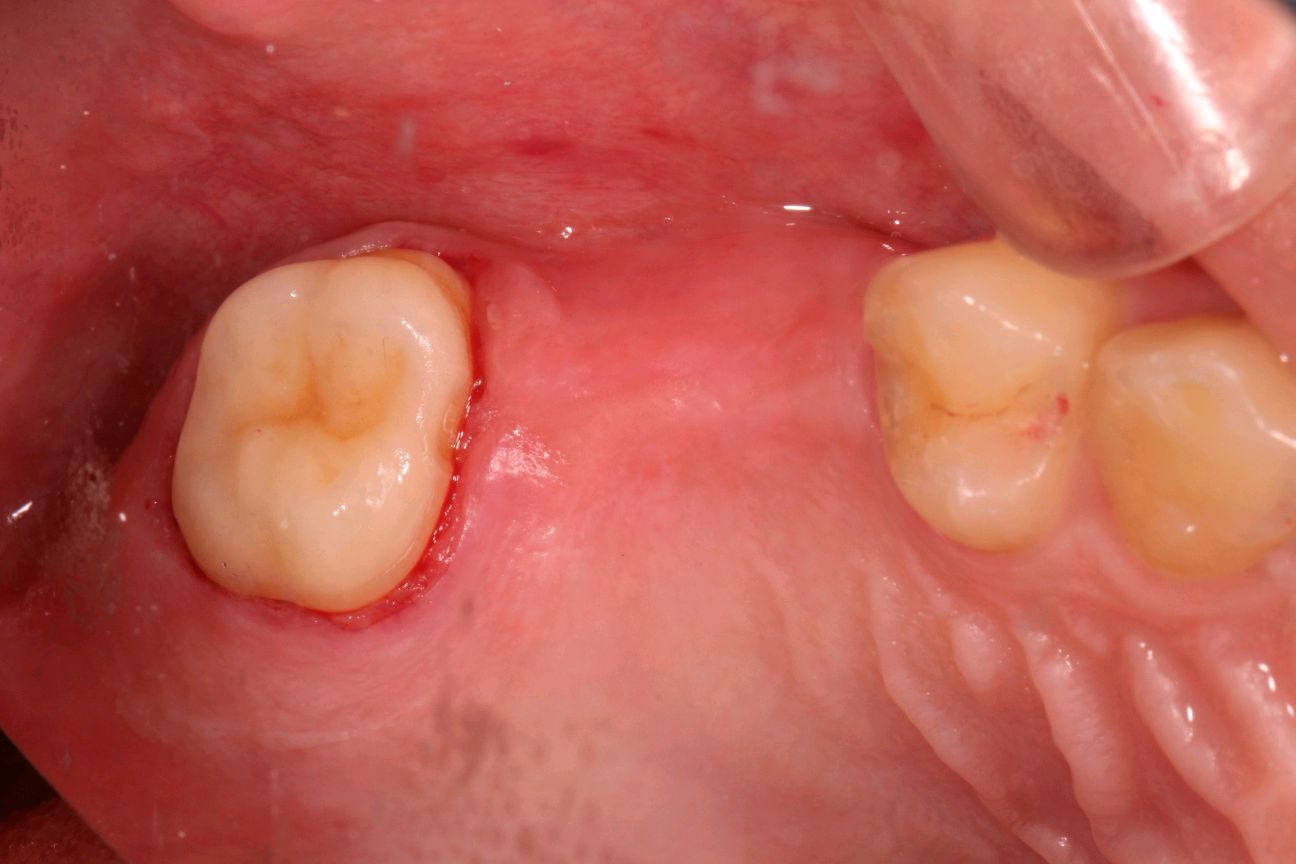

有图有真相:左上7根管治疗后高嵌体修复,采用CERCE扫描、切割、1小时修复完成,实现一次就诊当日修复完成!